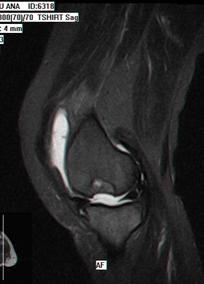

1.2.3. Rezonanta Magnetica Nucleara

Secventele standard T1 fast-spin nu sint sensibile in evaluarea leziunilor cartilajului articular, insa secventele T2 fast-spin si T1 densitate protonica cu supresie a grasimii sint atit specifice cit si senzitive in decelarea leziunilor cartilajului articular (fig. 1.5) Cea mai mare specificitate este la nivelul cartilajului articulatiei femuropatelare datorita grosimii cartilajului (fig. 1.6)

In Figura 1.9 si Figura 1.10 se pot observa leziuni de osteocondrita disecanta a condilului femural intern si extern, evidentiabile pe diferite sectiuni si secvente RMN.

Fig1.9 Imagine RMN sectiuni sagitale si transversala la nivelul genunchiului, leziune de osteocondrita disecanta a condilului femural intern |

In ultimii ani s-au dezvoltat noi tehnici RMN care sa creasca acuratetea diagnosticului leziunilor condrale, tehnici ce se bazeaza pe injectarea unor substante de contrast ce modifica proprietatile magnetice ale diferitelor componente ale matricii cartilajului. Cea mai folosita tehnica este cea in care se foloseste Gadolinium care permite masurarea continutului de glicozaminoglicani ai cartilajului: dGEMRIC (delayed gadolinium-enhanced MR imaging of cartilage) (fig. 1.11) [7, 26]. Prin injectarea i.v. de Gadopentetat Dimeglumina acidul Gadolinium Dietilenetriamin PentAcetic (Gd-DTPA) se acumuleaza la nivelul cartilajului articular invers proportional cu cantitatea locala de glicosaminoglicani. Regiunile cu cartilaj normal prezinta cantitati reduse de Gd-DTPA. Tehnica dGEMRIC poate evidentia atit leziuni condrale incipiente cit si gradul de maturare al tesutului cartilaginos de reparatie [39 ]